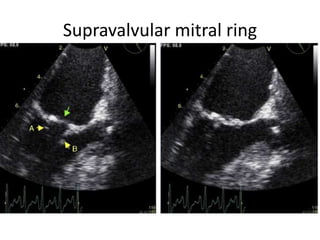

Supravalvular mitral ring

Mitral Stenosis etiology 1.Rheumatic: most common cause 2. Severe mitral annular calcification (MAC) 3. Congenital Parachute mitral valve: single papillary muscle to which chordae to both leaflets attach;results in mitral stenosis or mitral regurgitation Supravalvular mitral ring 4. Systemic diseases: can cause valvular fibrosis Carcinoid SLE RA Healed endocarditis